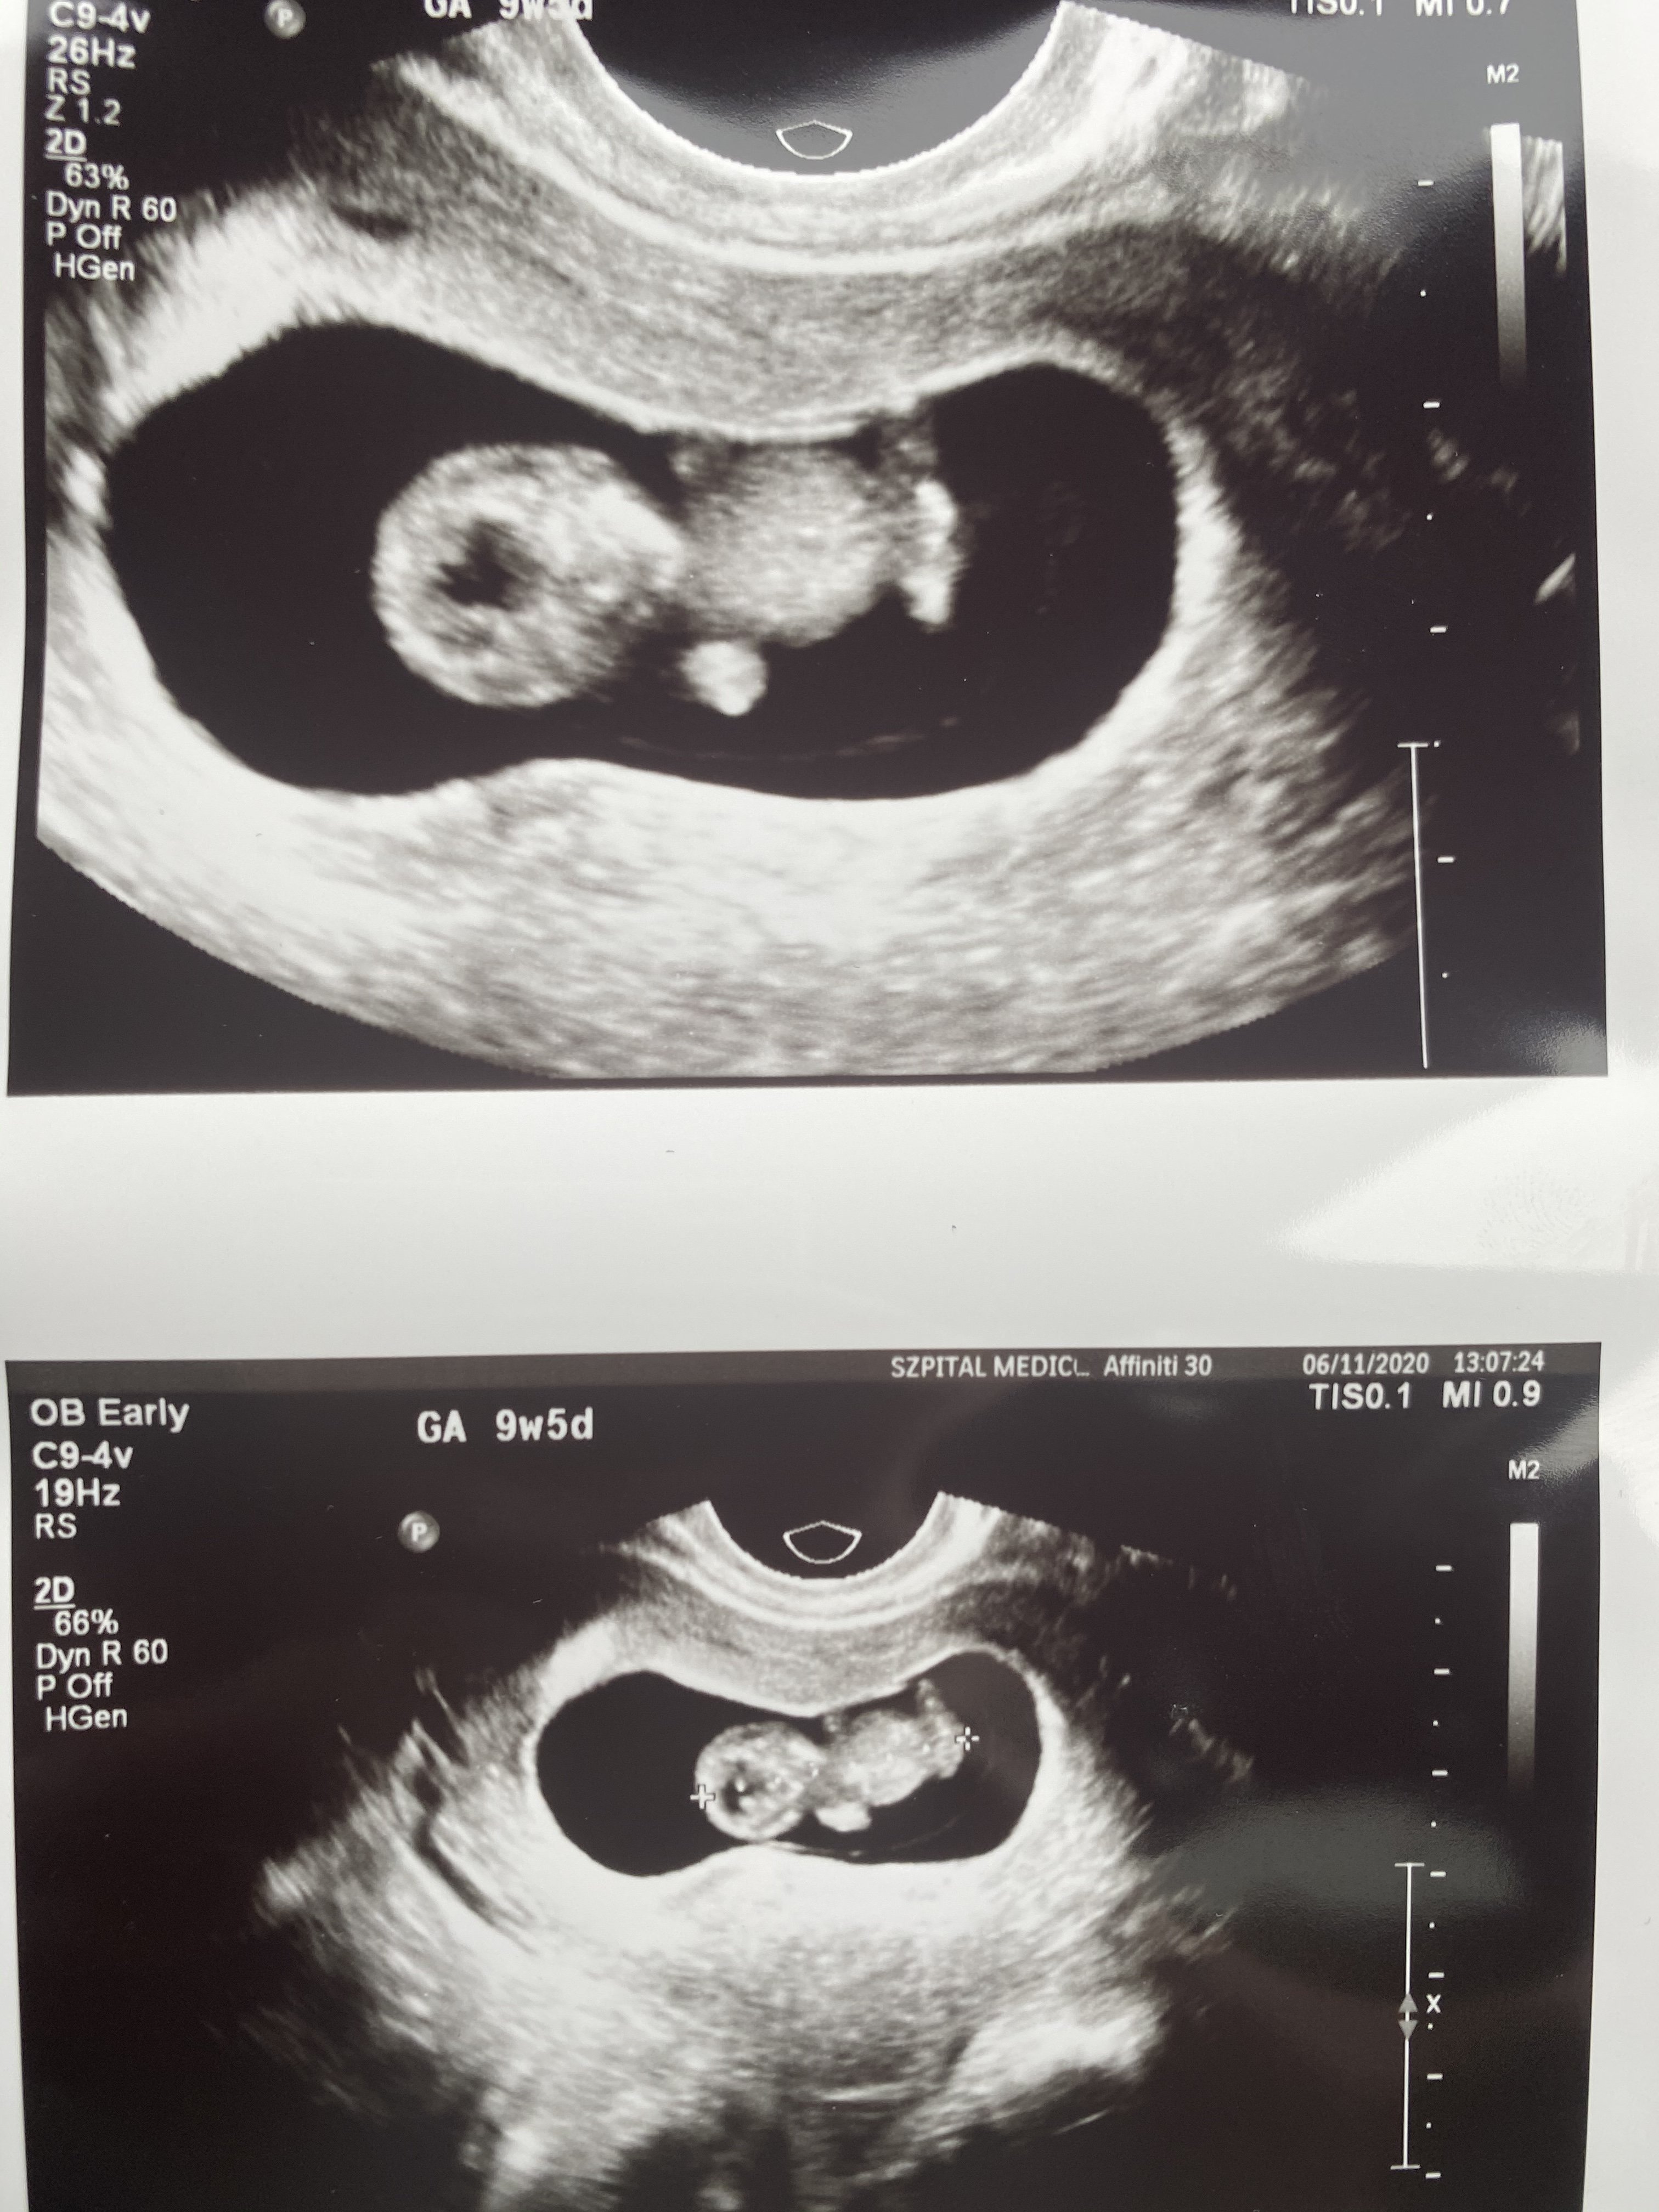

Trzymam z calegoKobitki to moje 2 cm szczęścia za tydzień robię Nifty pro, trzymajcie kciuki![]()